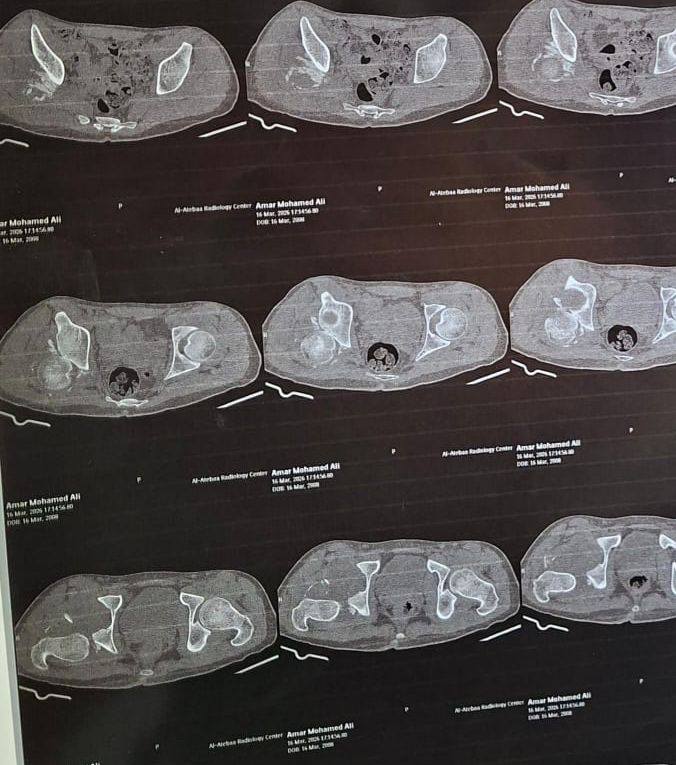

أ.د/ حسام الدين جاد – رئيس قسم جراحة العظام نجحت وحدة جراحات الحوض المتقدمة بقسم جراحة العظام والكسور في إجراء عملية معقدة لرد وتثبيت كسر مهمل بالجدار الخلفى للحق الحرقفى مع وجود خلع مهمل بالمفصل وتحرير العصب الوركى حيث انه حضر إلينا المريض يعانى من آلام فى الحوض وسقوط جزئى بالقدم بعد مرور شهرين من إصابته فى حادث وتم عمل اشعة فتبين وجود خلع مهمل مع كسر بالجدار الخلفى للحق الحرقفى بمفصل الفخذ وتم دخول الحالة للعمليات حيث تم استكشاف وتحرير العصب الوركى وعمل رد مفتوح للخلع وازالة التعظم بالانسجة المحيطة واعادة بناء الجدار الخلفى للحق باستخدام رقعة عظمية من داخل عظام الحوض وتثبيت الكسر بواسطة شرائح ومسامير وتم خروج المريض من العمليات بنجاح.